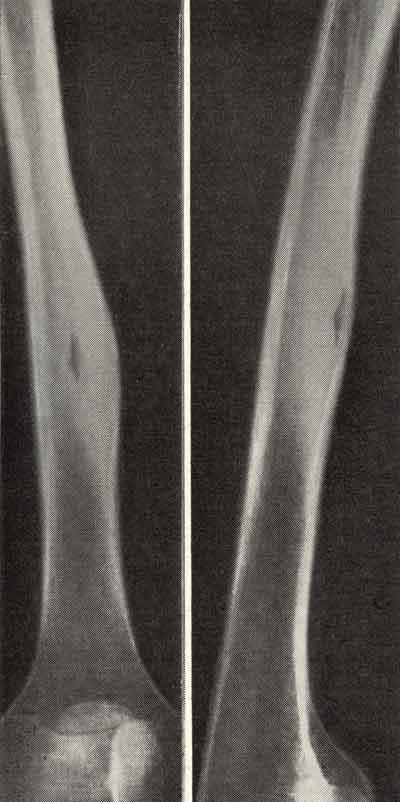

Какой вид перелома большеберцовой кости вы видите// Косой// Винтообразный// Прямой// Компрессионный// +Полифокальный

Какой синдром патологии костной ткани вы видите на данной рентгенограмме// Остеомаляция// Остеопороз// Остеосклероз// +Гипреостоз// Остеолизис

Какой синдром патологии костной ткани вы видите на данной рентгенограмме// +Остеомаляция// Остеопороз // Остеосклероз// Гипреостоз// Остеолизис